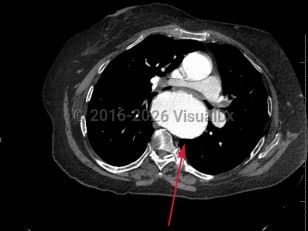

TAA is the dilatation of the artery compared to its original size; it is usually defined as the typical diameter of the artery increasing by 50%. A TAA will rarely manifest with symptoms, and about 95% of patients are asymptomatic. Catastrophic complications of TAA include aortic dissection and rupture, which are medical emergencies with high mortality rates. Most of these complications occur in the root or ascending aorta, followed by the descending aorta and aortic arch, respectively.

Biochemical and mechanical forces lead to TAA causing wall weakness and expansion. Changes in aortic wall compliance lead to increased stress on the artery and during systolic impulse can further exacerbate wall fragility, leading to aneurysms. Several factors that can lead to rupture or dissection include but are not limited to aortic ulcers (disrupted atherosclerotic plaques), intimal atherosclerosis, and intramural hematomas. Infectious aortitis can cause pseudoaneurysms (false aneurysms that occur at the site of arterial injury from infection or trauma).